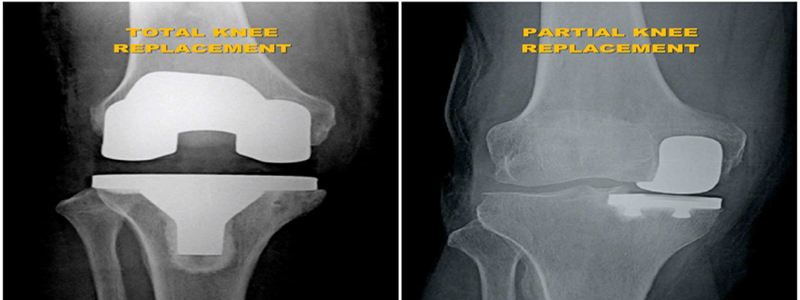

During the knee replacement surgery, the worn out surface (cartilage) of the joint is removed and is capped with implants called as endo-prosthesis. The femur and tibial sides are metal backed and in between there is polyethylene ‘insert’. The patella may or may not be replaced, depending upon the surgeon preference and condition of patellar cartilage.

The surgeon will make an incision on the top of your knee in order to expose the damaged area of your joint. The standard incision size can be as long as 10 inches, but a minimally invasive procedure can result in incisions as short as 6 inches. During the operation, the surgeon moves your kneecap aside and cuts away damaged bone and cartilage, which are then replaced with new metal and plastic components. The components combine to form a synthetic (but biologically compatible) joint that mimics the movement of your natural knee. Most knee replacement procedures take 30min - 1 hour to complete.